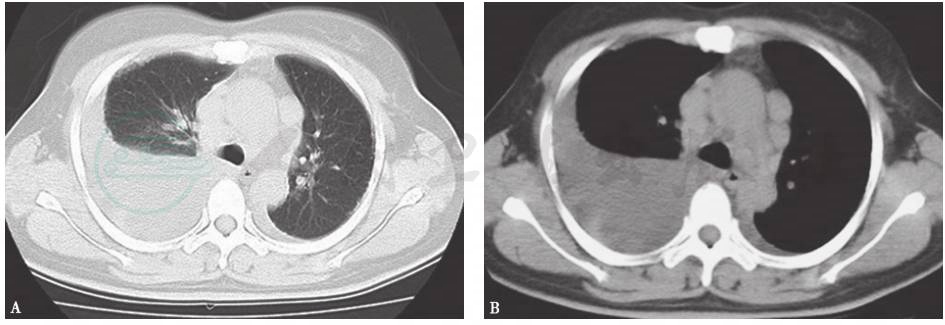

结合患者病史、临床表现及各项检查结果,本病例结核性胸膜炎诊断明确,并且考虑合并结节病。治疗方案采取异烟肼(isoniazid,INH)0.3g(每天1次)、利福平(rifampicin,RFP)0.45g(每天1次)、乙胺丁醇(ethambutol,EMB)0.75g(每天1次)、吡嗪酰胺(pyrazinamide,PZA)0.5g(每天3次)抗结核,同时给予激素治疗。患者症状缓解,出院后亦无不适主诉,坚持2HRZE/10HRE方案抗结核治疗,胸腔积液逐渐吸收。7周后复查胸部CT,发现纵隔淋巴结明显缩小(图13)。正规治疗1年后,患者停药,胸部CT提示纵隔肺门未见明显肿大淋巴结(图14)。

图13 治疗7周后复查胸部CT表现

胸部CT显示纵隔淋巴结明显缩小,胸腔积液明显吸收

引自:呼吸系统疑难病例诊疗辨析.第1版.ISBN:978-7-117-26415-0.主编:

图14 治疗1年后复查胸部CT表现